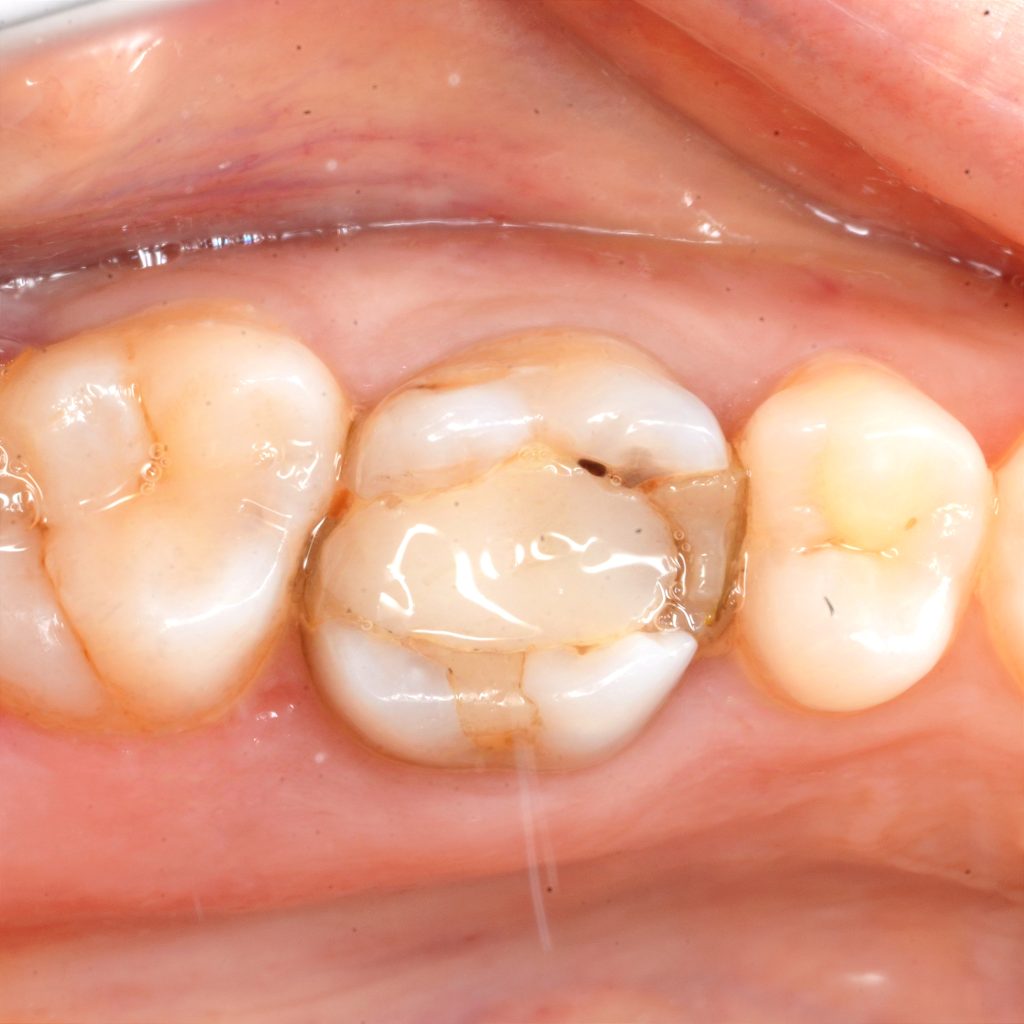

Isolation to build up and dme

After deep margin elevation

Take one month for healling

Ever x flo, cap in action

Ribbond around palatal wall to give more strength